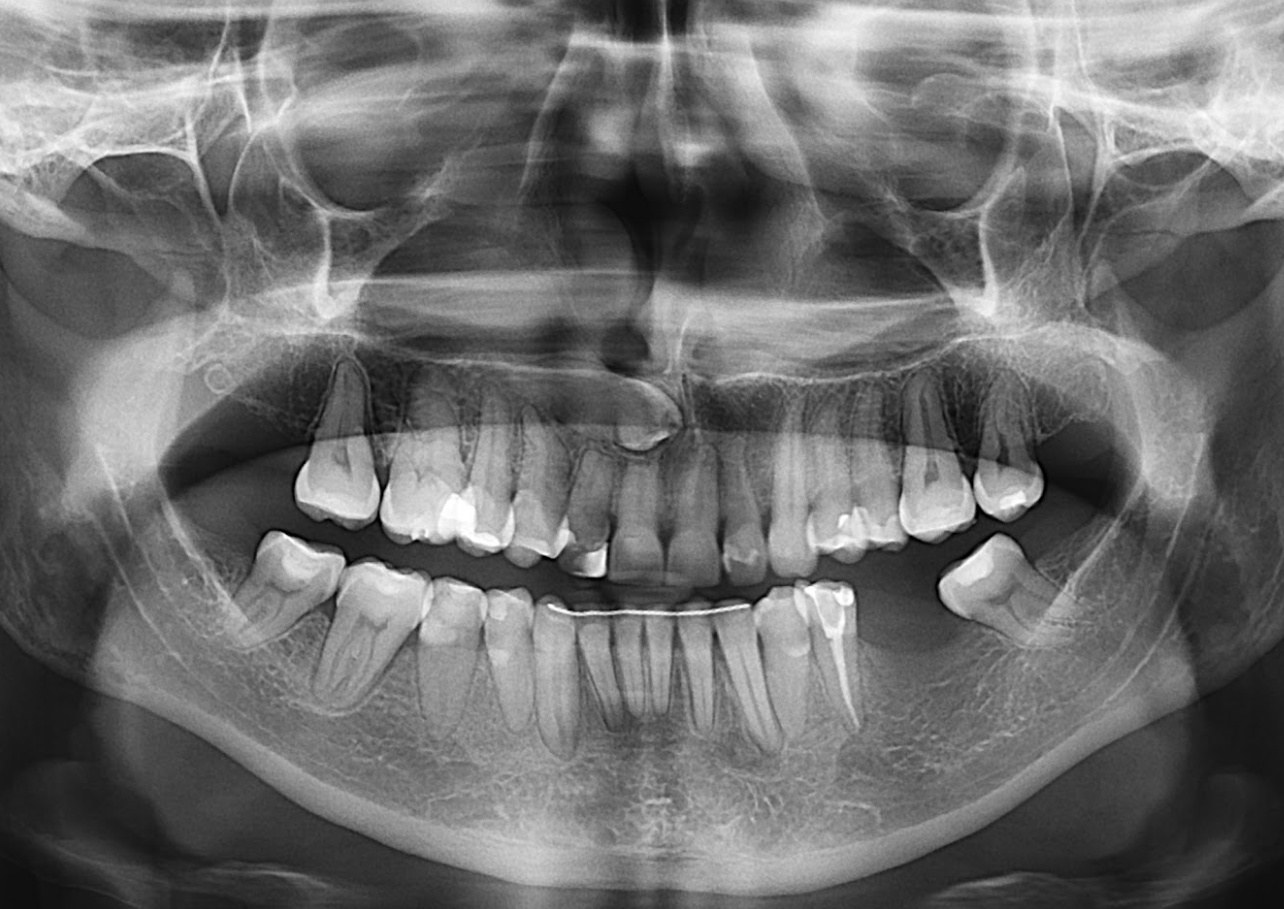

A la evaluación de la tomografía volumétrica (CBCT) en los cortes axiales (Figura 2) y transaxiales (Figura 3), se aprecia imagen mixta localiza a nivel apical de pieza 33 de limites definidos, que ocasiona adelgazamiento de tabla ósea lingual, así mismo se observa imagen mixta a nivel apical de pieza 35 y próximo a conducto dentario inferior, de limites definidos, que ocasiona adelgazamiento de tabla ósea vestibular

CORTES AXIALES